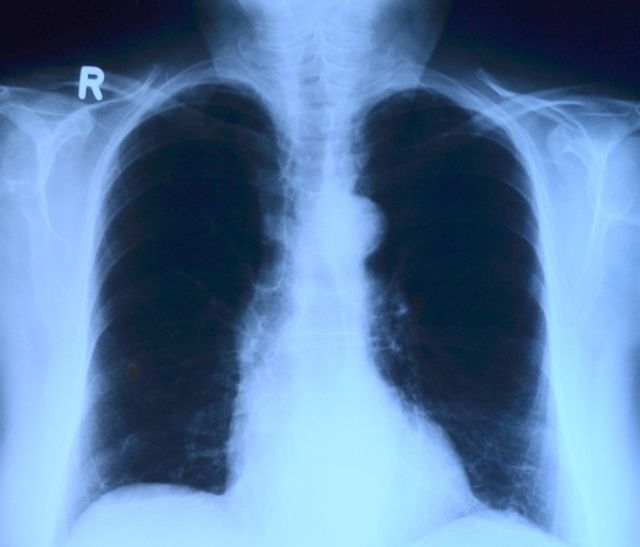

В комментарии ГУФСИН указано: «Схема лечения, назначенная осужденному пациенту, включала в себя антибактериальные препараты широкого спектра действия, которые применяются в том числе и для лечения бактериальной пневмонии. Противотуберкулезные препараты пациенту были необходимы, так как он был в контакте с больными туберкулезом. На фоне лечения рентгенологически от 22.03.2018 была положительная динамика».